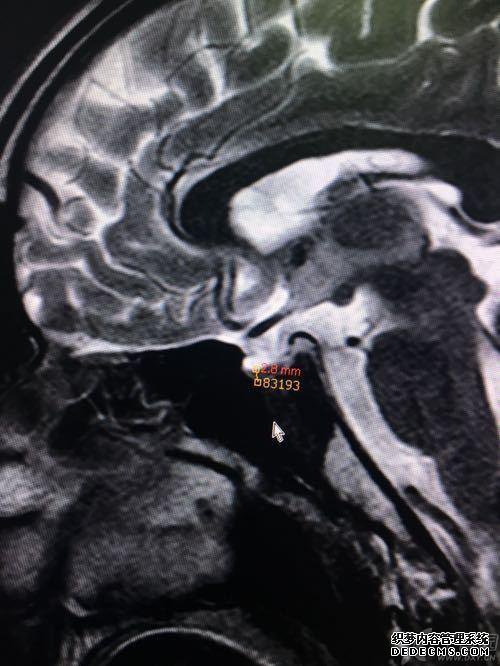

MRI扫描,椅子上充满了脑脊液信号

诊断,疾病是在晚期脑病发作的早期(脑垂体疾病在大脑中具有病理状态,发炎进入脑垂体并导致炎症下降)优势区域血液供应受损的病理改变是原始受影响神经的神经。

我需要发送MRI照片进行定向的帮助。